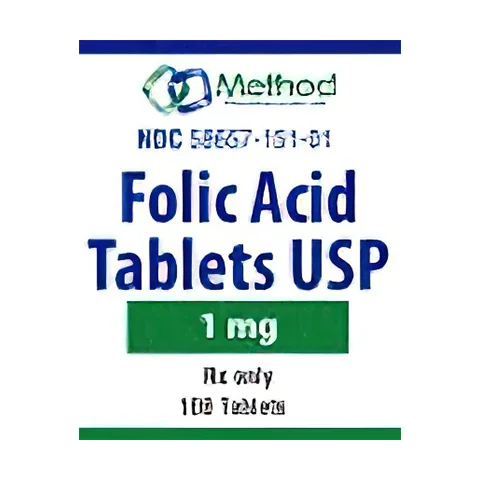

Featured products

Ready to deliver better care?

Explore our extensive range of cost-effective alternatives to popular medications tailored for your pharmacy.